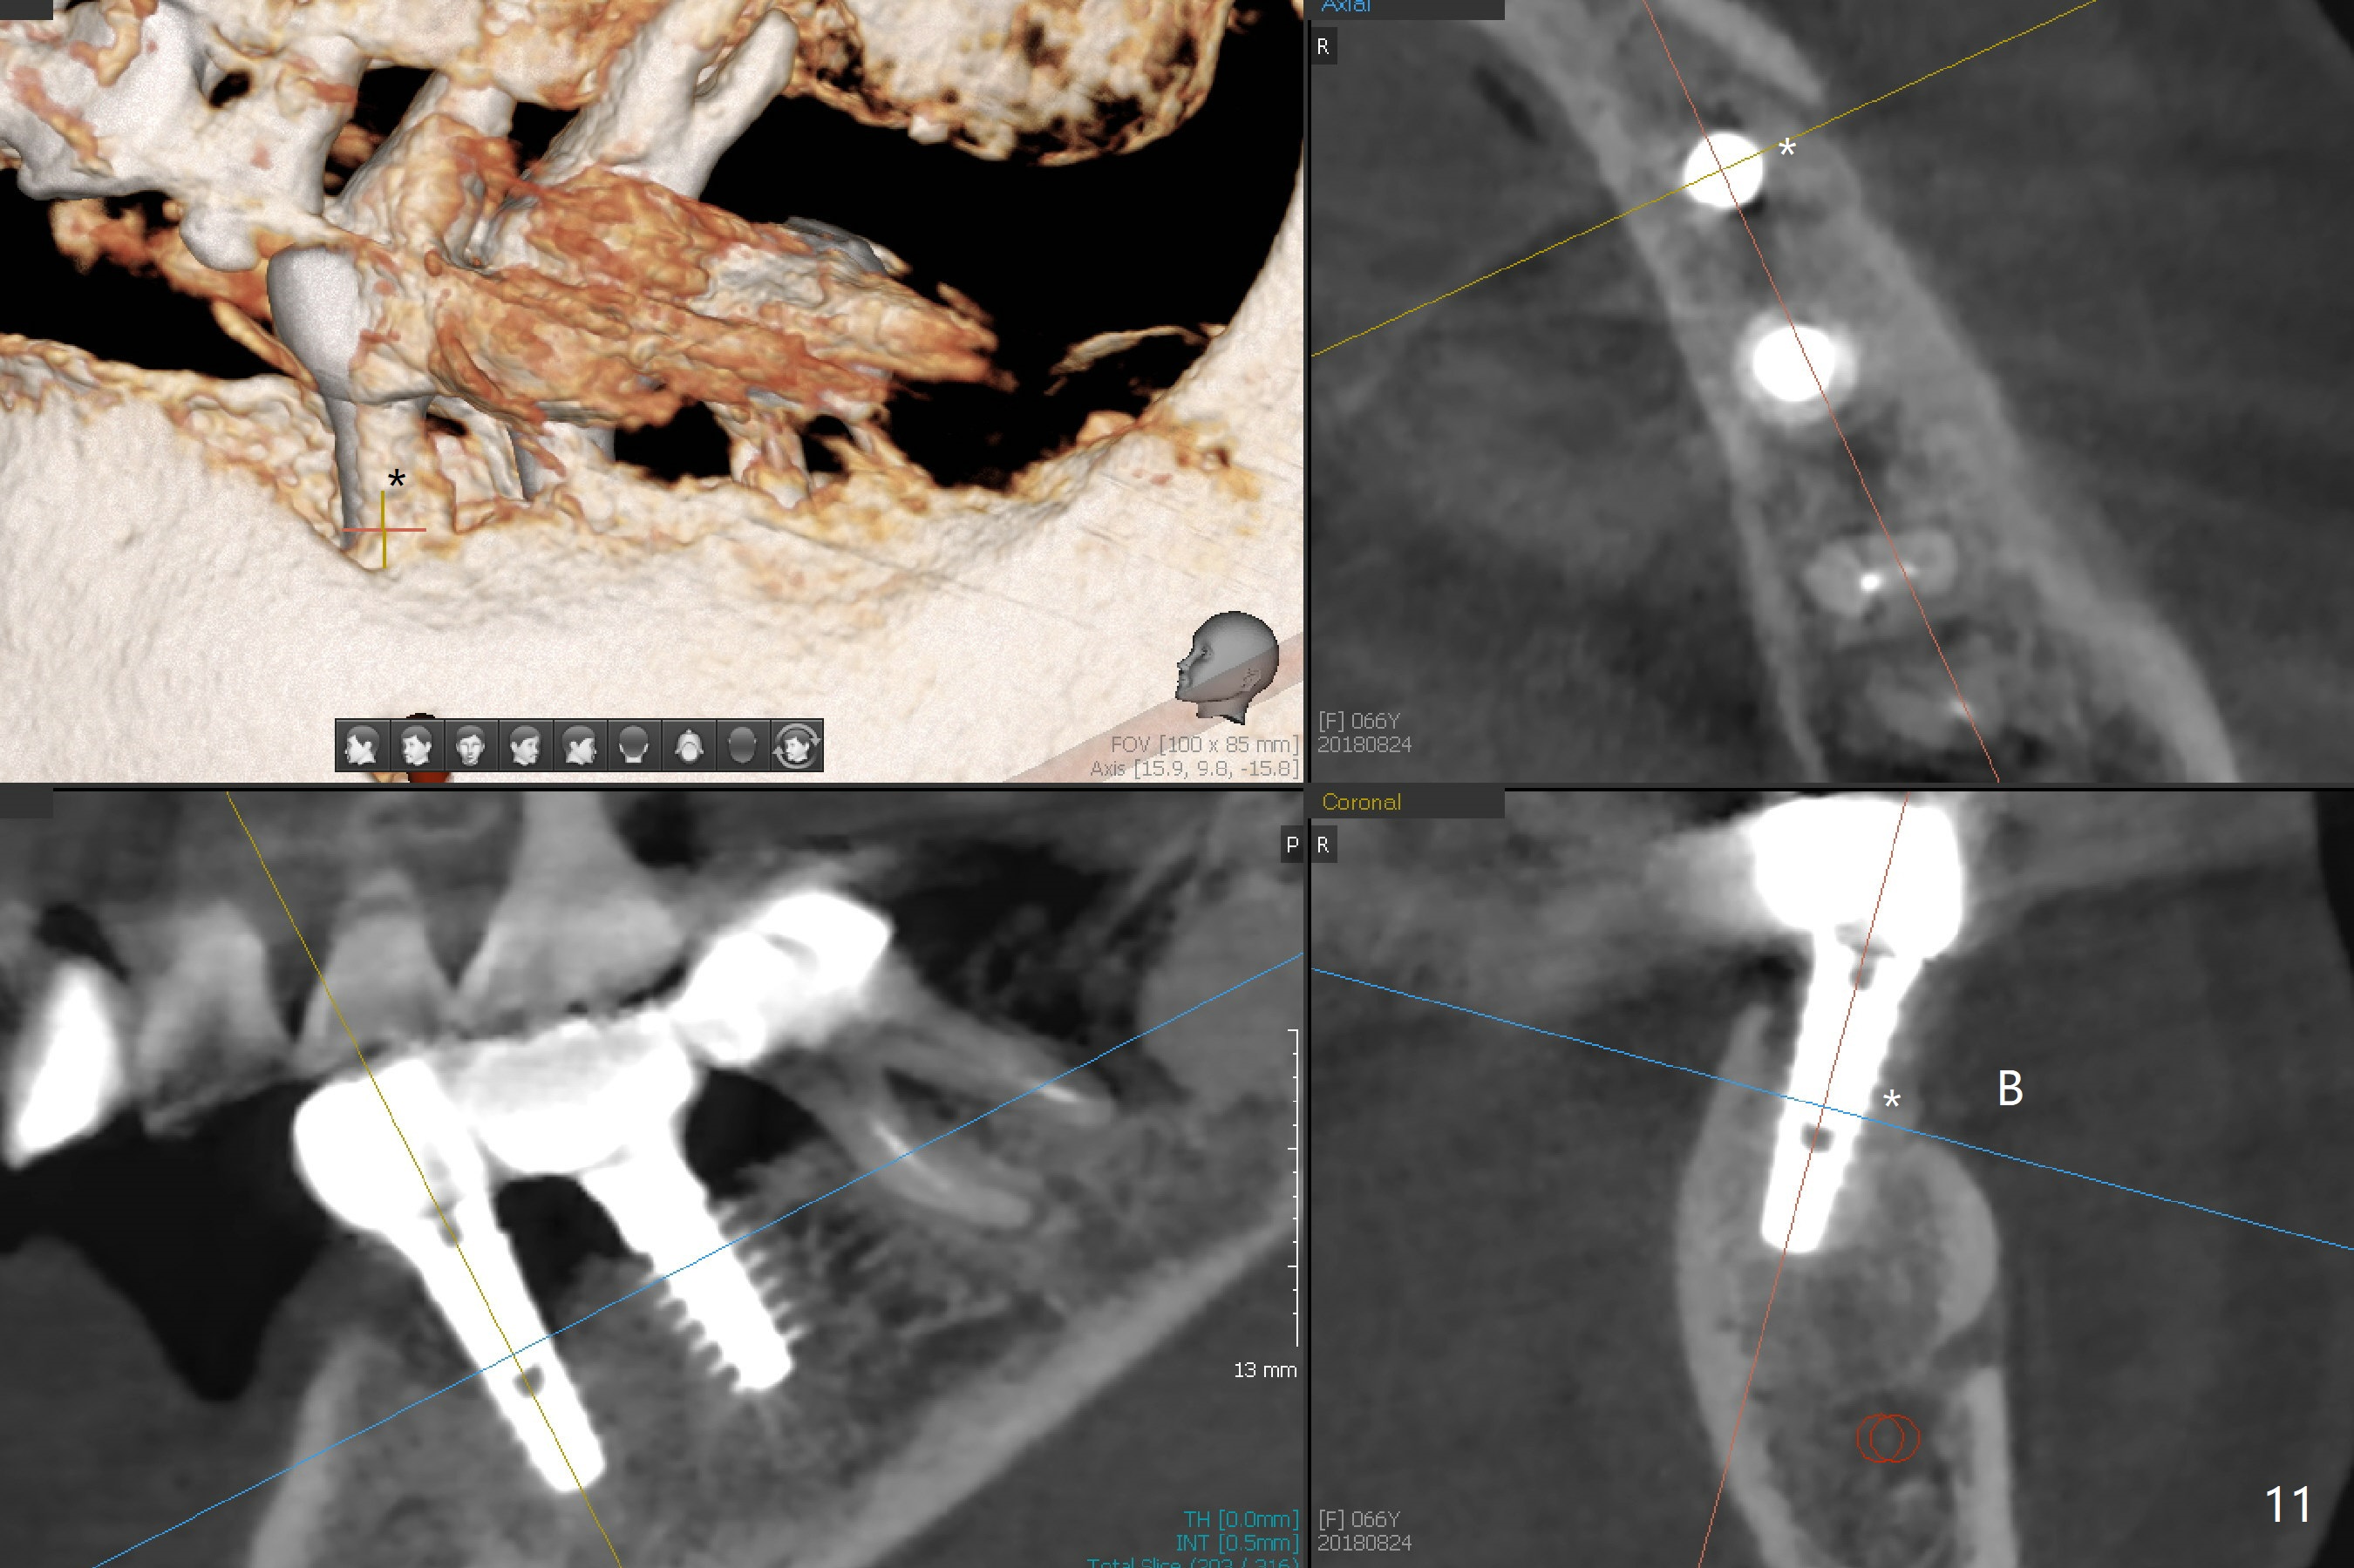

After removal of the pontic at #19 and retainer at #20 (Fig.1) and of vertically fractured root, the buccal plate is found to be defective (Fig.2 *). An implant will be placed as lingual as possible. Since the apex of the affected tooth is coronal to the Mental Loop (Fig.3 red dashed line), an osteotomy (Fig.4 yellow arrow) to be established in the mesial slope (blue dashed line) after extraction (black area) appears to be safer than that along the long axis of the tooth. The initial osteotomy is accomplished by free hand (Fig.5), but when the lower RPD is inserted, the superior end of the 1.5 mm pilot drill is distal (Fig.6). When the trajectory is corrected using the RPD as a surgical guide at the same depth (17 mm gingival level), brisk hemorrhage is from the osteotomy without severe pain. After hemostasis is achieved by packing the socket with Osteogen plug and bone graft and packing bone graft into the osteotomy, 3.3 mm Magic Drill is used for 14 mm. A 4x11 mm IBS implant is placed with 60 Ncm (Fig.7). The implant is then placed deeper, followed by placement of a 4.5x4(3) mm abutment and further bone graft (Fig.8). Finally the implant/abutment complex is apparently in an acceptable mesiodistal position with a large buccal gap which has been filled by bone graft (Fig.9 *). In fact the Mental Loop seems to have been not violated in the procedure (Fig.10). X-ray is taken 3 and 6 months postop. Bone graft (Fig.11,12 (CBCT) *) appears to remain over the buccal (B) surface of the implant coronally 13 months postop (7 months post cementation). The gingiva at #19 and 20 is apparently healthy 8 months post cementation except mild recession at #20 (Fig.13).